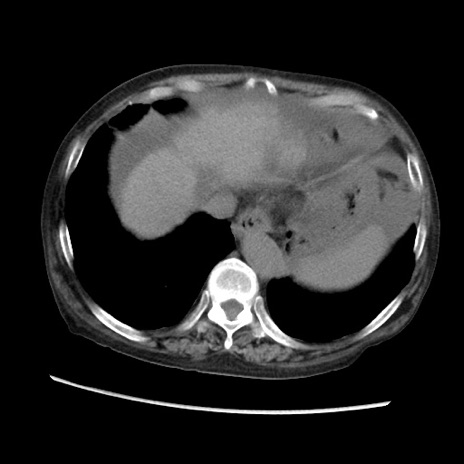

症例31(横断像)

【症例】80歳代 女性

【主訴】腹部膨満感

【現病歴】他院にて肝硬変にてフォロー中。1週間前から便秘、腹部膨満感、臍部腫瘤あり受診となる。

【既往歴】肝硬変

【身体所見】腹部膨隆あり、皮膚変化なし、疼痛なし。

【データ】WBC 4600、CRP 0.25